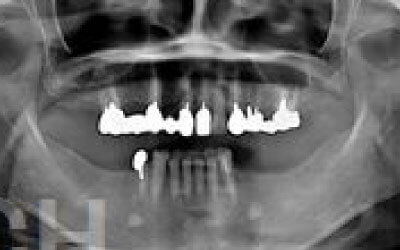

CTでは、骨や歯の状態を三次元で確認でき、正確な距離を測定することができます。

骨の厚さや傾き、神経の位置などを事前に詳しく計測することで、安全にインプラントを行うことができます。